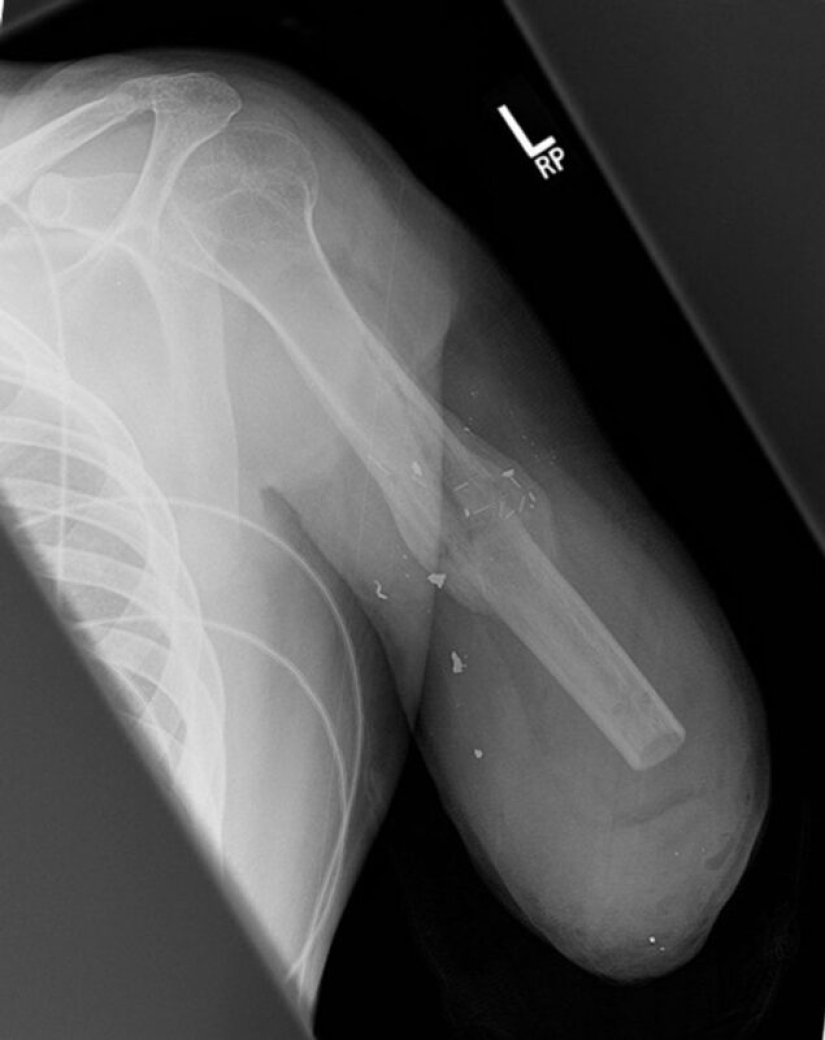

Así es como se ve el brazo en la radiografía después de la amputación